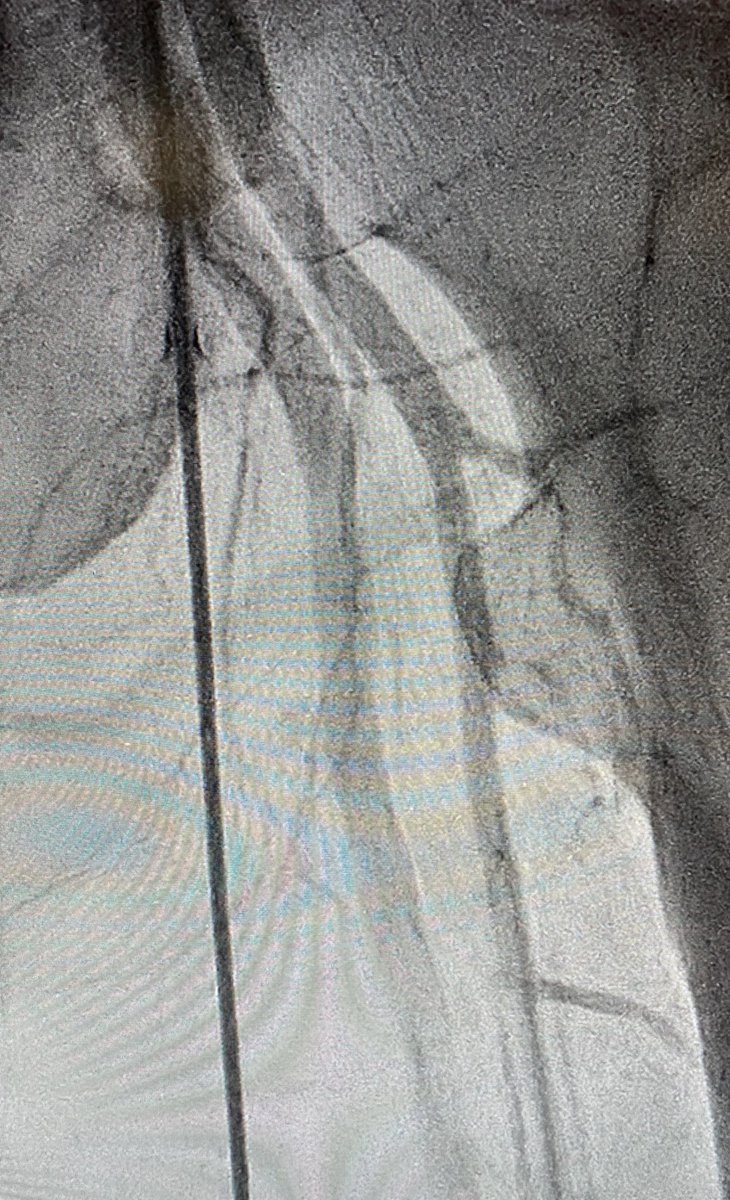

3/7 Impella observed going in. Take a moment to remove slack, achieve stable device position. Always place Swan with Impella in Shock...